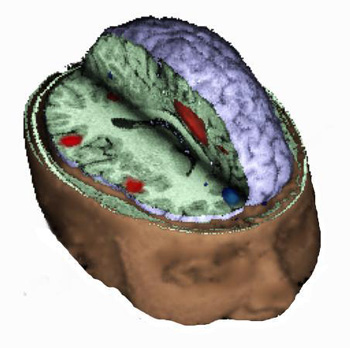

Caso 3

Niño diestro de 13 años de edad con epilepsia del lóbulo temporal. Se detectó un oligodendroglioma multiquístico en el lóbulo temporal izquierdo (flechas negras). Se indicó una IRM para llevar a cabo un mapeo de las áreas del lenguaje antes de la resección quirúrgica.

Una IRMf tridimensional muestra la masa en el polo temporal izquierdo. La activación se obtuvo mediante un paradigma de "tarea de repetición" (burbujas de color amarillo, anaranjado y rojo). La relación entre la lesión y las áreas del habla se muestra magníficamente.